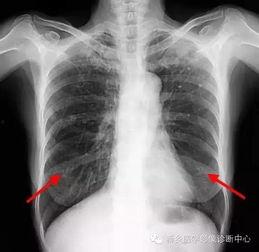

首先,得先弄清楚什么是胸片。胸片,顾名思义,就是通过X射线对人体胸部进行拍摄的一种医学影像检查。它能够清晰地显示出心脏、肺部、纵隔等器官的结构和形态,对于诊断各种胸部疾病有着至关重要的作用。

胸片检查是诊断肺部疾病的重要手段。通过观察肺部影像,医生可以初步判断患者是否患有肺炎、肺结核、肺癌等疾病。